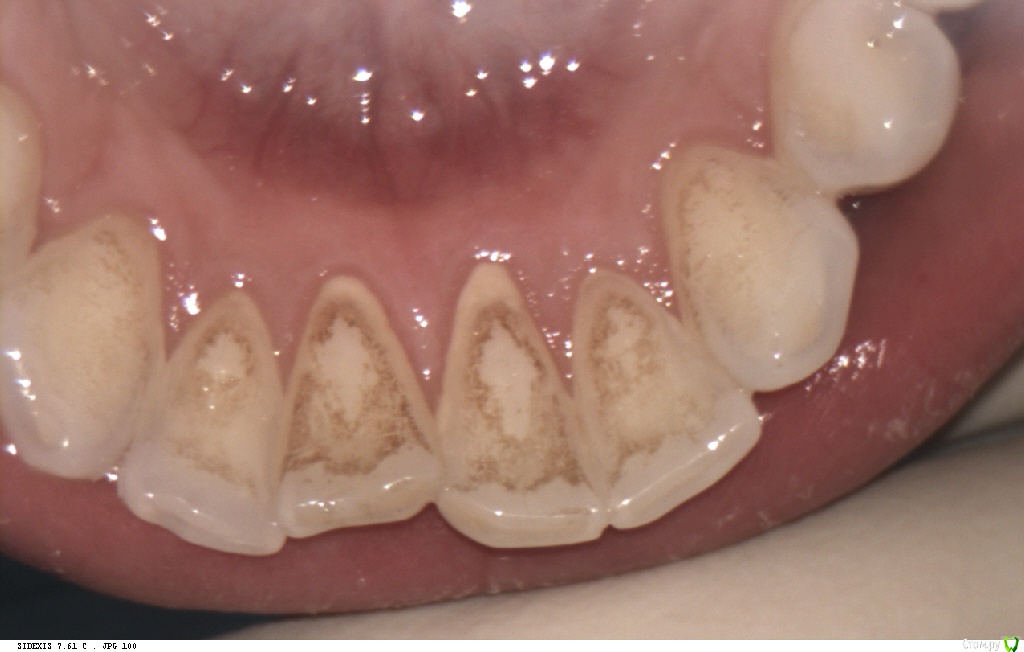

Pan Опубликовано 6 мая, 2017 Поделиться Опубликовано 6 мая, 2017 (изменено) типичная локализация кариеса при плохой гигиене и злоупотреблении в питании фастфуда. Ну понятно, что всё это на фоне сниженной кариесрезистентности. Первым делом нужно объяснить девушке значимую роль питания и гигиены в развитии кариозных процессов. Изменено 6 мая, 2017 пользователем Pan 1 Ссылка на комментарий

Pan Опубликовано 11 мая, 2017 Поделиться Опубликовано 11 мая, 2017 (изменено) Деструкция эмали (в типичных для зубного налета местах) произошла значительно ранее ( разве нужно еще раз говорить об истинных причинах, способствующих этому процессу?) Потом, конечно, индивидуум (взрослея) изо всех сил старается и отсутствие признаков гингивита(если хотите) тому подтверждение. Но, увы, процесс уже запущен... Вы конечно же не хотите оспорить тот факт, что деструкцию эмали (кариес) вызывают бактерии зубного налета. Изменено 11 мая, 2017 пользователем Pan Ссылка на комментарий